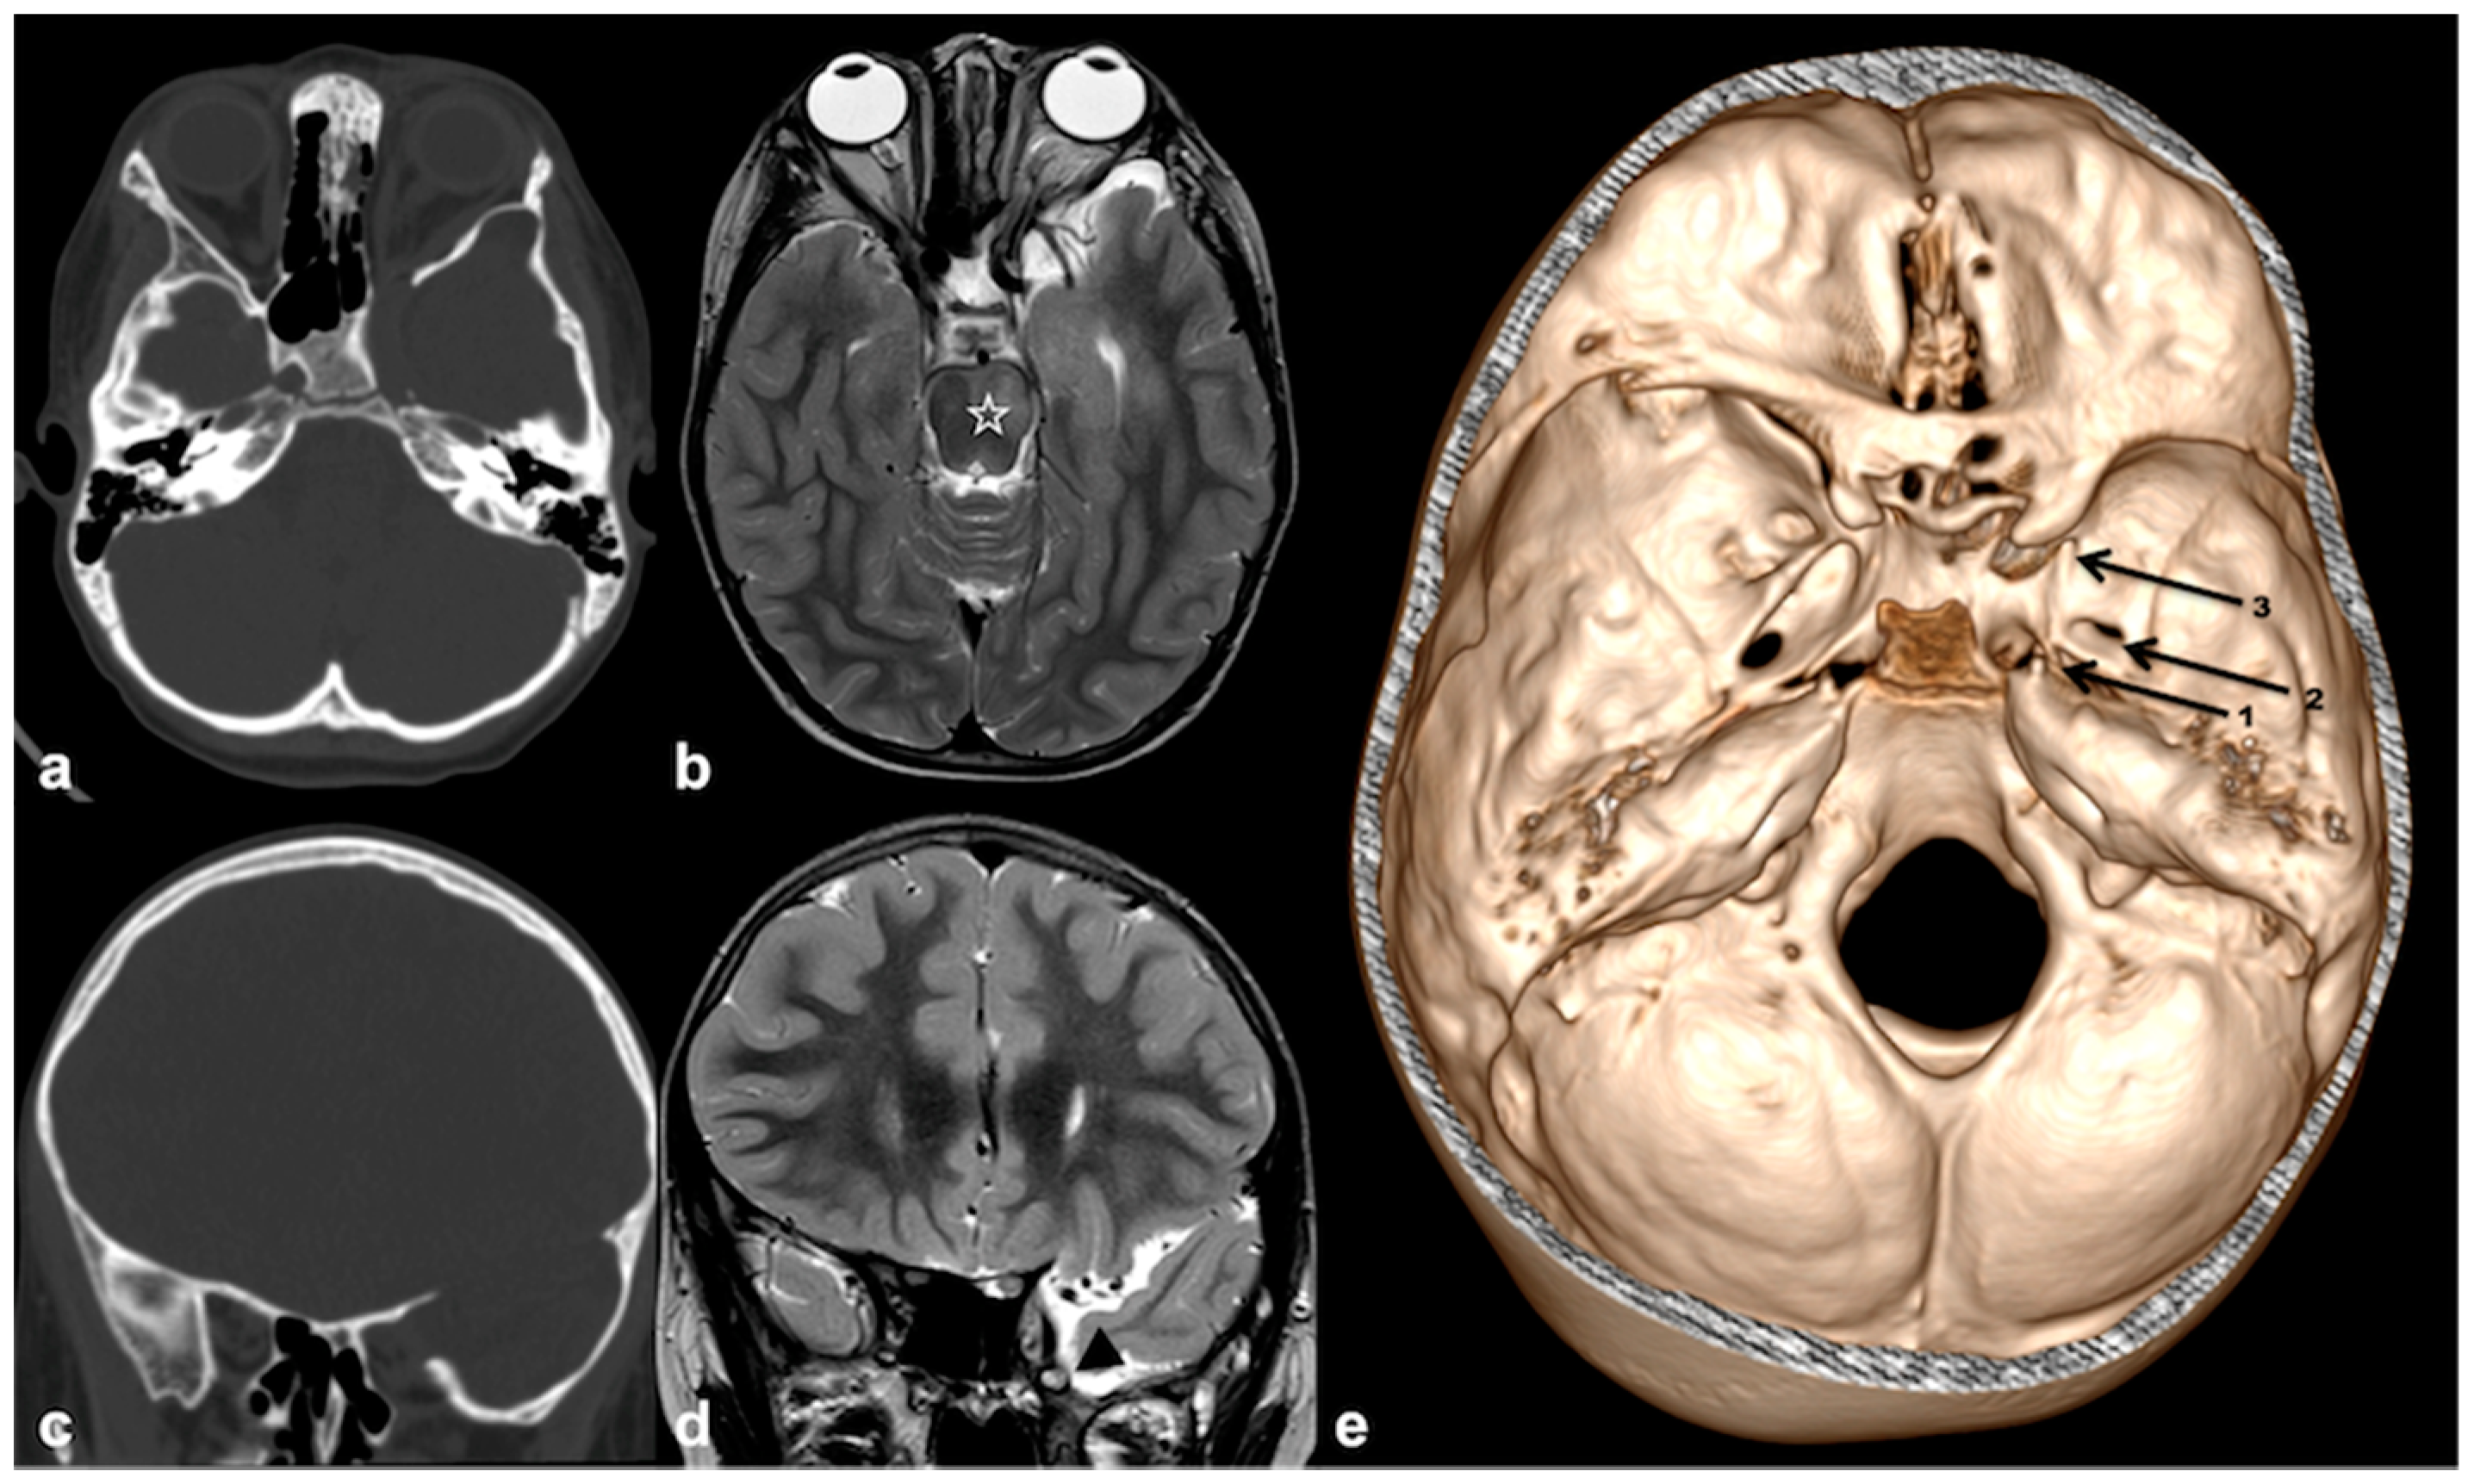

3. Skull and Orbit

3.1. Sutural Defects

3.2. Skull Bone Defects and Associated Dural Dysplasia

3.2.1. Sphenoid Wing Dysplasia

3.2.2. Imaging Manifestation of Orbital Involvement